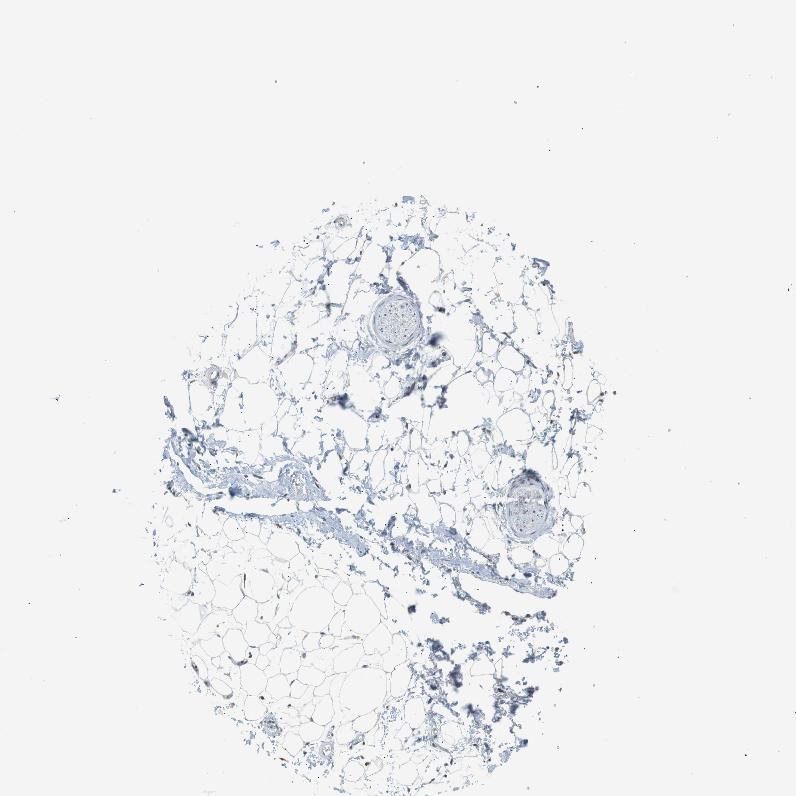

SOFT TISSUE 1 - Antibody stainingi

Antibody staining in the annotated cell types in the current human tissue is reported as not detected, low, medium, or high, based on conventional immunohistochemistry profiling in selected tissues. This score is based on the combination of the staining intensity and fraction of stained cells.

Each image is clickable and will lead to virtual microscopy that enables deeper exploration of all samples and also displays staining intensity scores, fraction scores and subcellular localization as well as patient and tissue information for each sample.

Antibody HPA015701

Fibroblasts Not detected

Peripheral nerve Low

SOFT TISSUE 2 - Antibody stainingi

Peripheral nerve Not detected